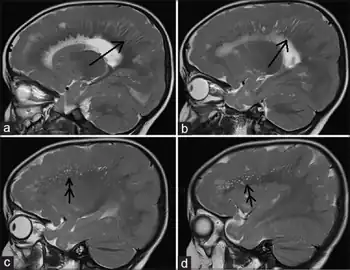

a, b)MRI shows radial stripes arrow c,d) show scattered dots in form of hyperintensities arrow | |